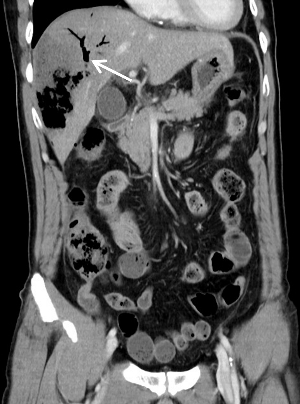

今晨零点左右上厕所后再发畏寒发热,家属发现其口唇发紫、呼吸急促,遂来本院急诊。腹部CT平扫提示肝内积气(图 2)。收住急诊抢救室,急查腹部增强CT,考虑肝脓肿致肝脏破裂(图 3)。

| 图 3 患者冠状位增强CT提示肝内胆管积气(箭头所指处) |